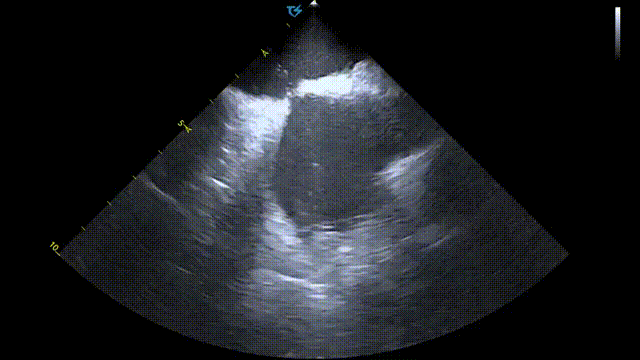

术前术后心包对比:

术前心包基线扫描

术后心包检查